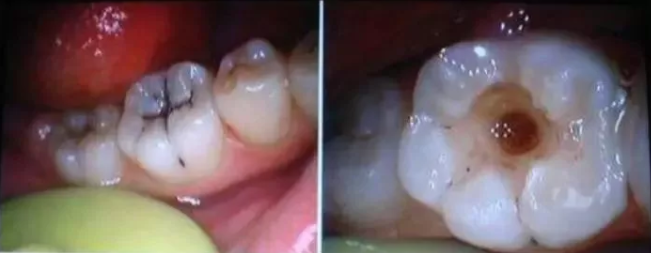

我长得太早了,以致于好多人以为我是乳牙,蛀了也不去理会,牙医叔叔阿姨们经常会看到这样的我,我很难过,也很痛。

如果我变成这样了,要赶紧去找牙医叔叔阿姨们,尽早治疗。